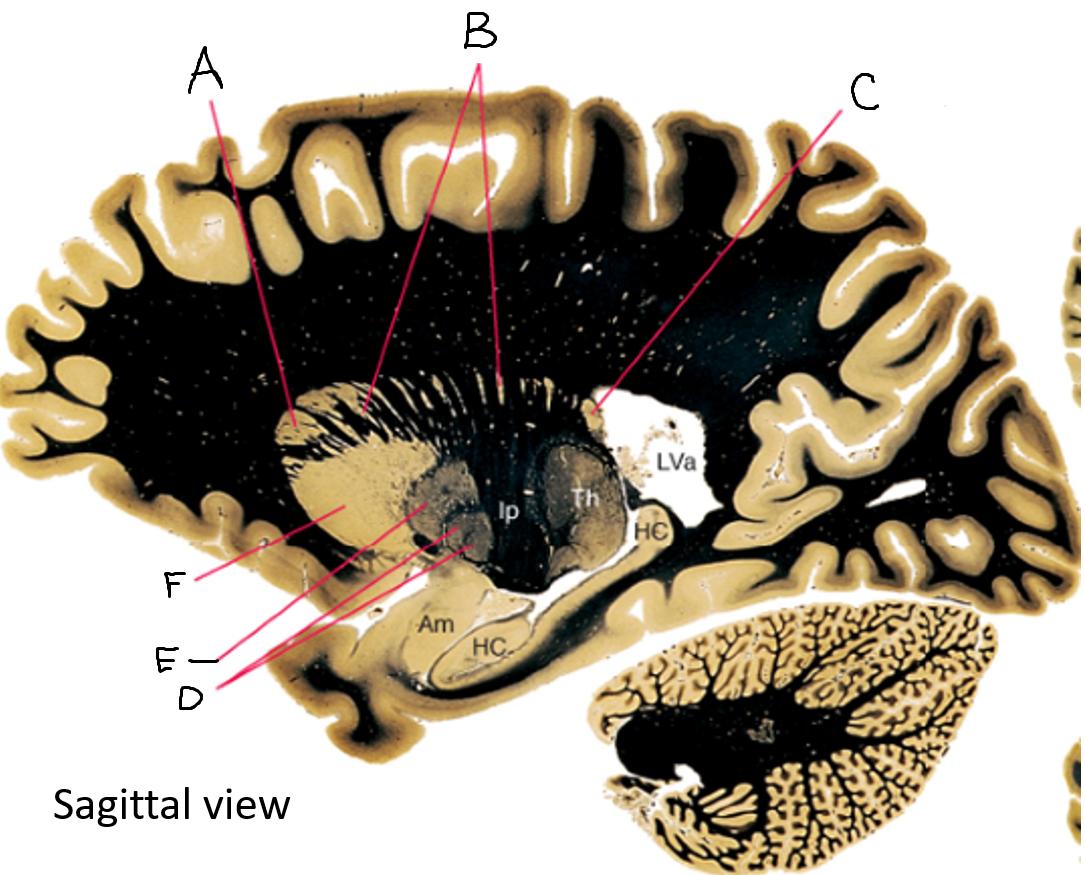

basal ganglia

A

somatosensory cortex

B

parietal association cortex

C

frontal and prefrontal cortices

D

primary motor cortex

E (where are the projections?)

putamen

F (where are the projections?)

caudate

A

caudate nucleus head

C

caudate tail

D

globus pallidus (internal segment)

E

globus pallidus (external segment)

F

putamen